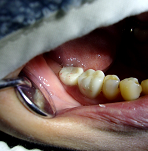

歯科治療の一例

レントゲン診査 インプラント処置 無痛治療の例

提携 歯科技工所への発注 口腔外科疾患に対する処置

歯科口腔外科用器具による処置 歯肉処置の例

口腔外科に準じた処置 インプラントの埋入手術(上顎)

歯科補綴物の装着